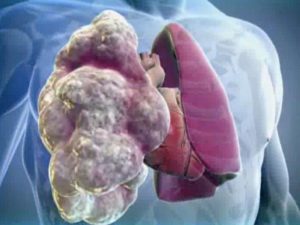

Как и другие органы человеческого организма, легкие подвержены многим заболеваниям. Одним из таких является буллезная болезни легких (буллезная эмфизема), которая характеризуется расширением конечных ветвей бронхиол. В результате в легких образуются буллы (воздушные кисты).

Буллезная болезнь легких относится к хроническим обструктивным заболеваниям. Характеризуется образованием воздушных участков, из-за которых альвеолы увеличиваются в размерах, и начинается разрушение их стенок.

Этот процесс стимулирует образование полостей диаметром более 1 см, в которых скапливается воздух, что приводит к нарушению циркуляции легких. У мужчин болезнь диагностируется в 2 раза чаще, чем у женщин. Основная часть пациентов приходится на пожилой возраст.

Буллы в органах могут достигать 10 см в диаметре. В этом случае их называют гигантскими. Они бывают единичными и множественными. Гигантские буллы начинают сдавливать легочные ткани, ухудшая газообмен в органе.

Если буллы достигают гигантских размеров, они могут сдавливать функционирующие участки легкого, вызывая нарушение функции дыхания. Признаки дыхательной недостаточности могут определяться у больных с множественными, двусторонними буллами, а также буллезной болезнью, протекающей на фоне диффузной эмфиземы легких.